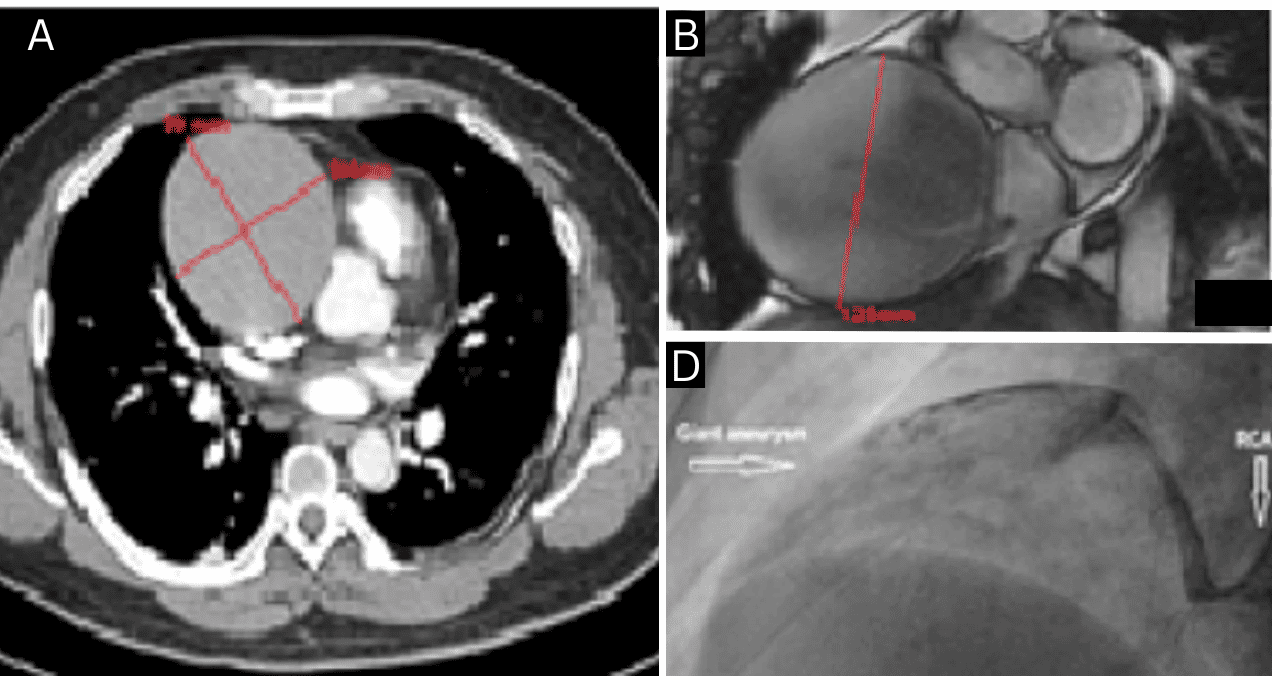

Hombre de 40 años presenta aneurisma gigante de arteria coronaria derecha asociado a consumo de drogas

El aneurisma fue inicialmente sospechado como una posible fístula aorta-aurícula derecha.